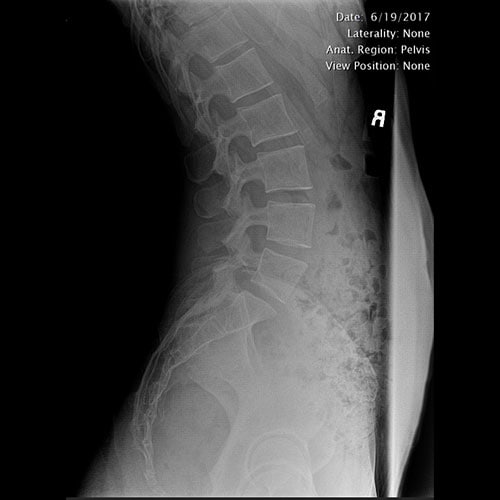

Normal lat lumbar